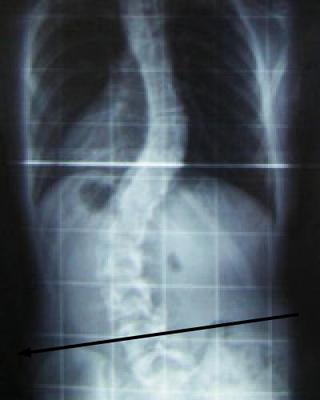

I have been having pain in my lower back left side for the past 2-3 months after I started running and exercising a lot after a long period of inactivity. Prior to that I was having a lot of tightness/tension in the middle of my back on the right side. I found out I have scoliosis of about 10 degrees or less which causes the tightness. I have left lumbar scoliosis. Also I have uneven hips as a result of the scoliosis. The right hip is higher than the left.

I'm afraid that with a spine looking like the leaning tower of Pisa, stresses and strains are inevitable at the apex of the curves.

Whilst exercise will help strengthen the muscles, and keep the joints mobile, only a lift in your shoe can straighten you up; then all the other issues will show vast improvement. It's so simple and inexpensive; why go looking for a costly and less effective solution?